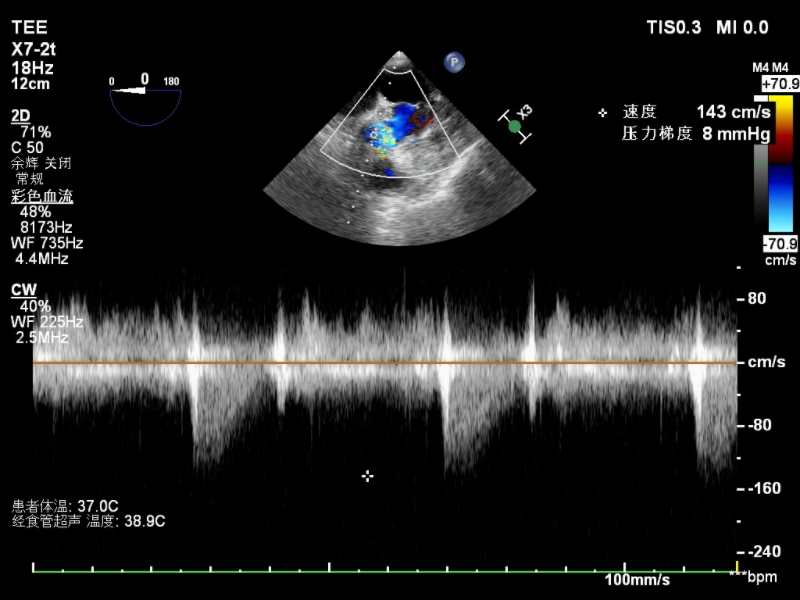

一切准备就绪后,手术按计划实施。由张海波教授主刀,在心脏大血管外科副主任刘仕强、陈旭主任医师、王永杰副主任医师的辅助下,在手术室、重症监护室的密切配合下,团队使用患者自体心包制作成主动脉瓣瓣叶,顺利完成Ozaki手术。术中超声可见自建主动脉瓣开关良好,未见狭窄及反流,Vmax:1.4m/s,Max PG:8mmHg(图2)。

图2